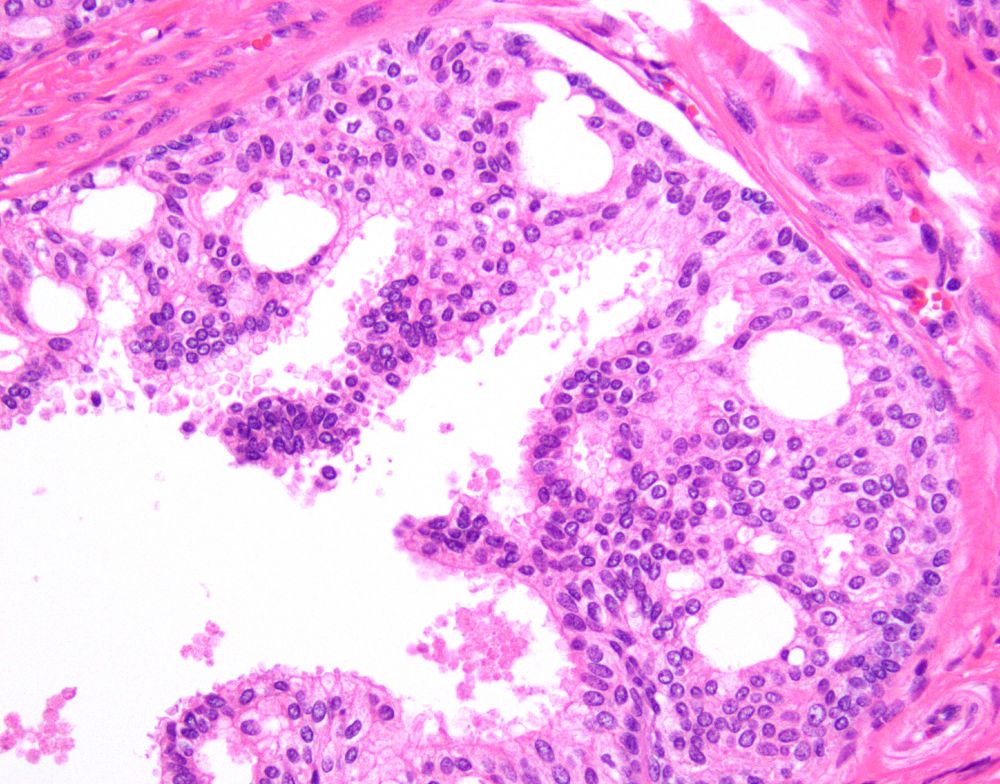

FNA of solid pancreatic head mass.

What do these cells represent?π§π§

A) Acinar cell carcinoma

B) Neuroendocrine tumor

C) Pancreatoblastoma

D) Solid pseudopapillary neoplasm